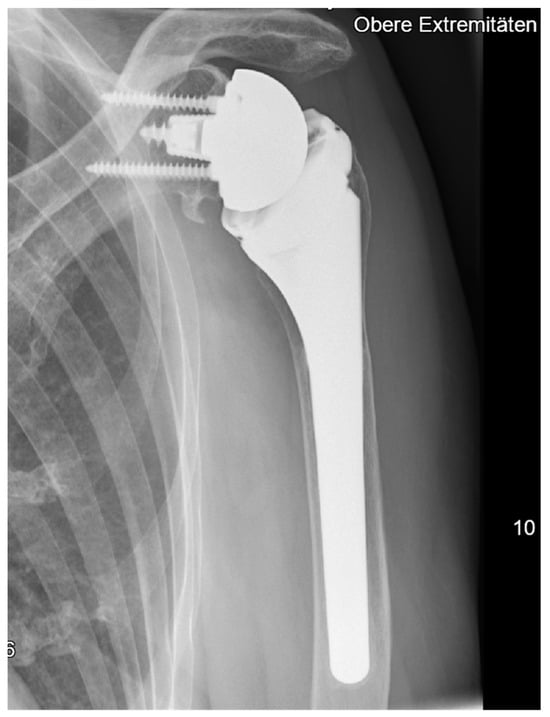

All patients were treated with RSA using the Univers Revers prosthesis with a 135° NSA (Arthrex, Naples, FL, USA; Figure 1) combined with the Universal Glenoid (Arthrex, Naples, FL, USA). The design of this prosthesis is based on the usage of a rectangular metadiaphyseal locking stem that is combined with a metaphyseal cup which be used centered or with either 2 mm left or right offset according the humeral diaphysis. This humeral inlay design is further completed by the usage of a standard or constrained +3 mm or +6 mm humeral polyethylene liner that offers adaptation to the glenosphere diameters’ different concavity depths (jump heights) from 9.8 mm (36 mm standard) to 13.9 mm (42 mm constrained) and following stability ratios of 193–194% using a standard liner as well as stability ratios of 277–300% using constrained liner designs [].

Figure 1.

Example at the five-year follow-up after reverse shoulder arthroplasty with 135° NSA and a cementless metadiaphyseal fixation stem (Univers Revers, Arthrex, Naples, FL).